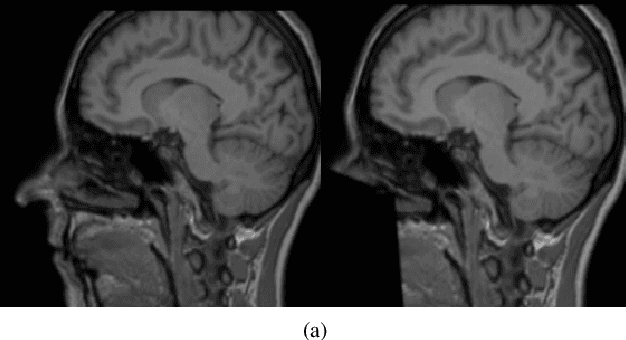

Abstract:Recent advancements in the field of magnetic resonance imaging (MRI) have enabled large-scale collaboration among clinicians and researchers for neuroimaging tasks. However, researchers are often forced to use outdated and slow software to anonymize MRI images for publication. These programs specifically perform expensive mathematical operations over 3D images that rapidly slow down anonymization speed as an image's volume increases in size. In this paper, we introduce DeepDefacer, an application of deep learning to MRI anonymization that uses a streamlined 3D U-Net network to mask facial regions in MRI images with a significant increase in speed over traditional de-identification software. We train DeepDefacer on MRI images from the Brain Development Organization (IXI) and International Consortium for Brain Mapping (ICBM) and quantitatively evaluate our model against a baseline 3D U-Net model with regards to Dice, recall, and precision scores. We also evaluate DeepDefacer against Pydeface, a traditional defacing application, with regards to speed on a range of CPU and GPU devices and qualitatively evaluate our model's defaced output versus the ground truth images produced by Pydeface. We provide a link to a PyPi program at the end of this manuscript to encourage further research into the application of deep learning to MRI anonymization.